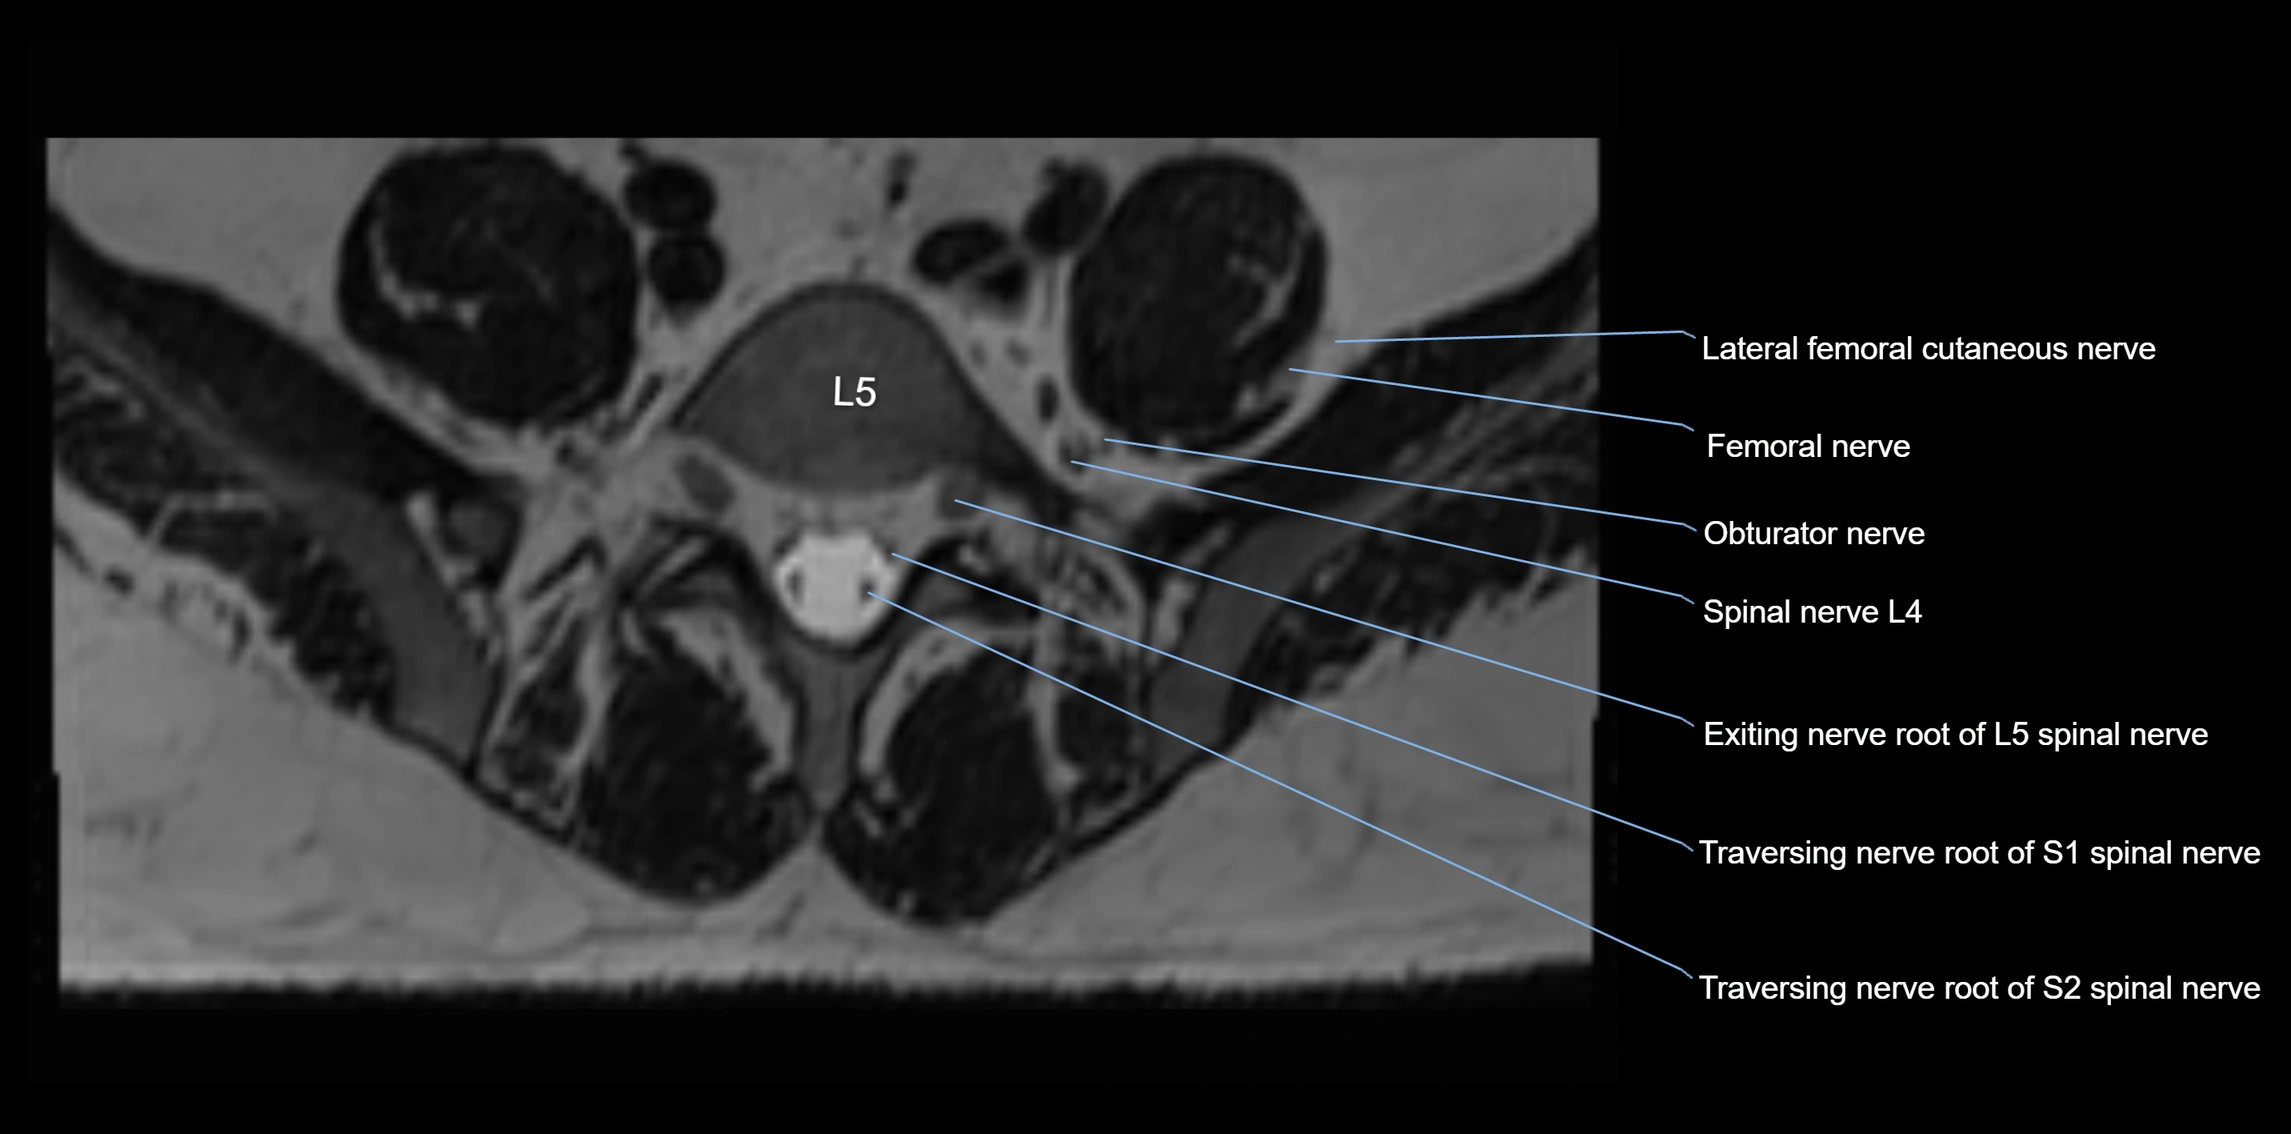

MRI image

image